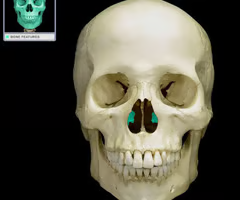

Frontal bone

Maxilla bone

Zygomatic bone

Nasal bone

Lacrimal bone

Inferior nasal conchae

Greater wing of the sphenoid bone (“sphen”=wedge)

Perpendicular plate of the ethmoid bone (helps form bony nasal septum with vomer)

Vomer

Optic canals (optic nerve)

8

How many bones are in the cranium?

1 frontal bone, 2 parietal, 1 occipital, 2 temporal, 1 ethmoid, 1 sphenoid

What are the bones in the cranium?

Ethmoid bone

14

The facial bones are made up of how many bones?

1 mandible, 2 maxilla, 2 zygomatic, 2 nasal, 2 lacrimal, 2 palatine, 1 vomer, 2 inferior nasal conchae

What bones are in the facial bones?